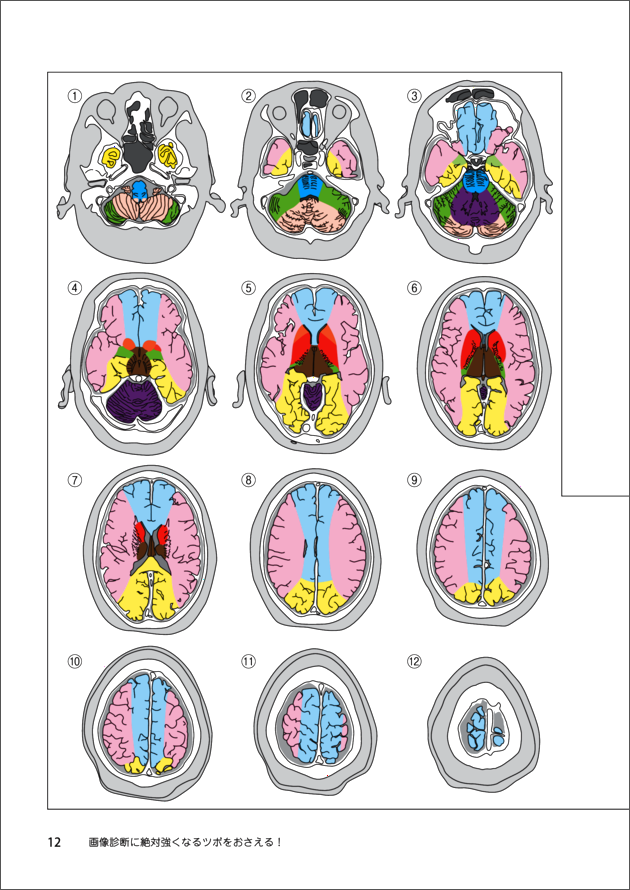

1 脳のvascular territoryと脳葉の画像解剖